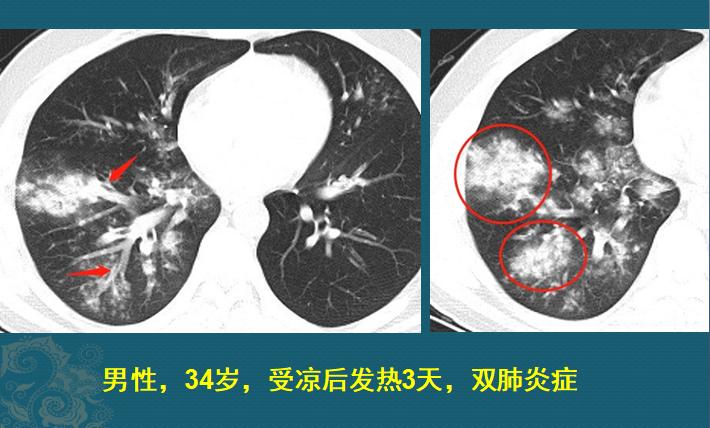

这是一位34岁的已婚男,受凉以后发热、咳嗽3天,体温最高39℃,伴有咽喉疼、气短,在家吃莲花清瘟胶囊和罗红霉素效果不明显,过来做了肺部CT,双侧肺炎(右侧重):

此时属于肺炎初期,CT片上以支气管周围炎为主,沿着支气管分布的白色斑片影,提示吸入性感染,但此时CT表现缺乏特征性,比如支原体肺炎、细菌感染、真菌或者病毒性肺炎都可以有这种初期表现,以支原体肺炎最常见,需要结合化验检查和病原学检测来判定致病菌,不同病菌需要不同的抗菌药物。